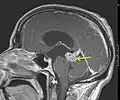

1. Astrocitoma de bajo grado del mesencéfalo (lámina tecti), resonancia magnética sagital ponderada en T1 después de la administración de medio de contraste: el tumor está marcado con una flecha. Los espacios del LCR frente al tumor se expanden debido a la hidrocefalia interna inducida por compresión..